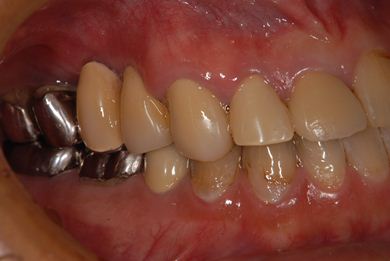

インプラントの症例写真 IMPLANT

インプラント治療

| 治療方針 | 左下欠損部分をインプラント治療にて機能的・審美的回復を行う。 | ||||||||||||||||||||||||||||||||

| 治療内容 | インプラント2本、ハイブリッドセラミッククラウン2本 | ||||||||||||||||||||||||||||||||

| 総治療費 | 399,000円 | ||||||||||||||||||||||||||||||||

| 治療期間 | 9ヶ月 |